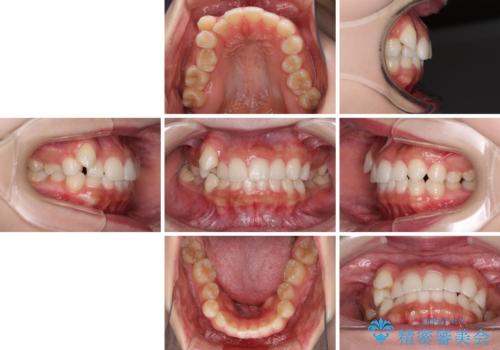

- 八重歯を気にして来院された患者様です。

本来であれば八重歯の隣後方の歯を抜歯するのですが、その後ろの歯が乳歯であり後続永久歯もなかったため、乳歯を抜去することとしました。